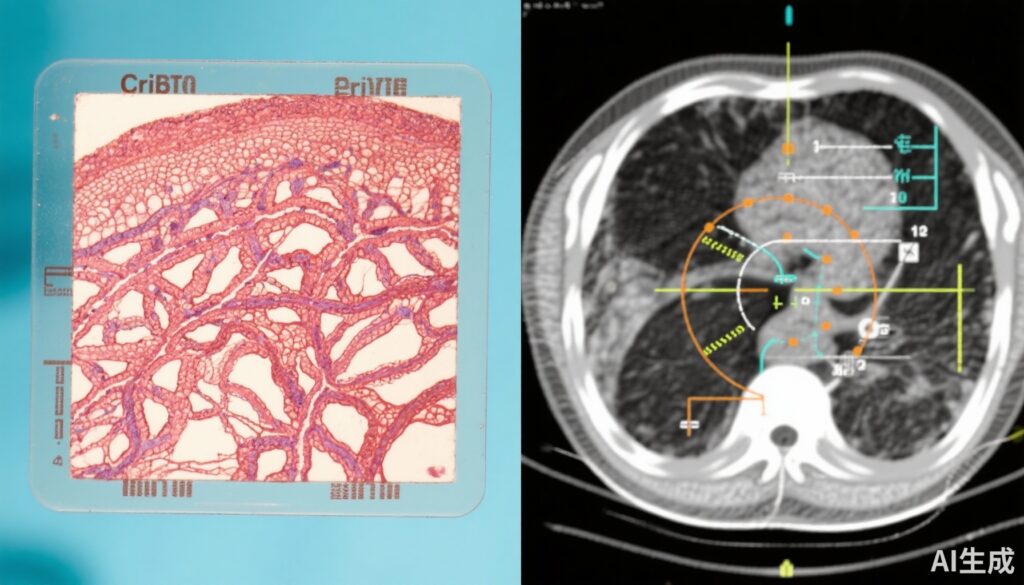

PROTECT試験は1999年から2009年にかけて実施された画期的な第3相無作為化臨床試験で、局所進行前立腺がんの男性1,643人を登録しました。参加者は、積極的監視、根治的前立腺切除術(手術)、または放射線療法と新規補助ホルモン療法(ADT)の組み合わせのいずれかの管理戦略に無作為に割り付けられました。この二次解析では、中央病理学的評価のために利用可能な712人の男性の生検標本を後方的にレビューしました。診断生検スライドで侵襲性篩状がんおよび/または管内がんが確認された患者は篩状陽性と分類されました。主要エンドポイントは、15年以内に画像またはPSA値が100 ng/mLを超えることにより確認された骨、臓器、またはリンパ節への転移でした。意図治療解析とプロトコル解析の両方が実施され、年齢、PSA値、グレーソンスコア、治療割り当てなどの重要な変数を調整しました。

分析された712人の男性(平均年齢62歳)のうち、93人(13.1%)が篩状陽性で、42人(5.9%)が追跡期間中に転移を発症しました。篩状形態の存在は、転移リスクの強力な独立した予測因子でした。具体的には、篩状陽性患者は篩状陰性患者と比較して、転移のハザード比(HR)が3.61(95% CI, 1.60-8.11; P = .003)でした。

治療法に関しては、新規補助ADTと組み合わされた放射線療法は、篩状陽性患者の転移リスクを大幅に低下させました(HR 0.35, 95% CI 0.16-0.78; P = .04)。これにより15年間の累積転移発生率は約8%となりました。手術は積極的監視と比較して転移を遅らせましたが、長期的な転移リスク低減については統計的有意性に達しませんでした(HR 0.52, 95% CI 0.25-1.08; P = .09)。15年間の累積発生率は、手術で約26%、積極的監視で約25%でした。篩状形態を持たない患者では、すべての治療法において転移率が低く、有意な差は示されませんでした。これは、積極的監視などの保守的な管理戦略を支持しています。